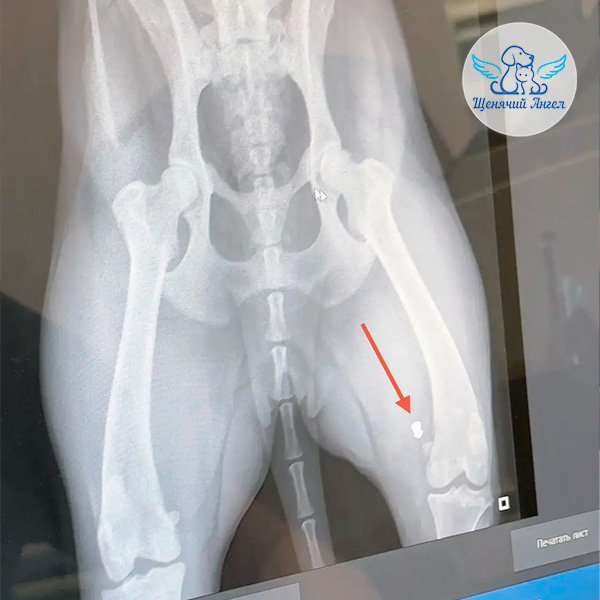

🩻 Снимок показал, что у малышки пуля в области коленного сустава, в нижней части бедра.

По мнению хирурга, в момент выстрела был повреждён нерв – именно поэтому Варя не может полноценно управлять лапкой. Сама пуля, вероятнее всего, сейчас не оказывает прямого влияния: она находится в проекции кости, а нерв проходит под ней. Удаление возможно, но не является срочным или обязательным ☝🏻